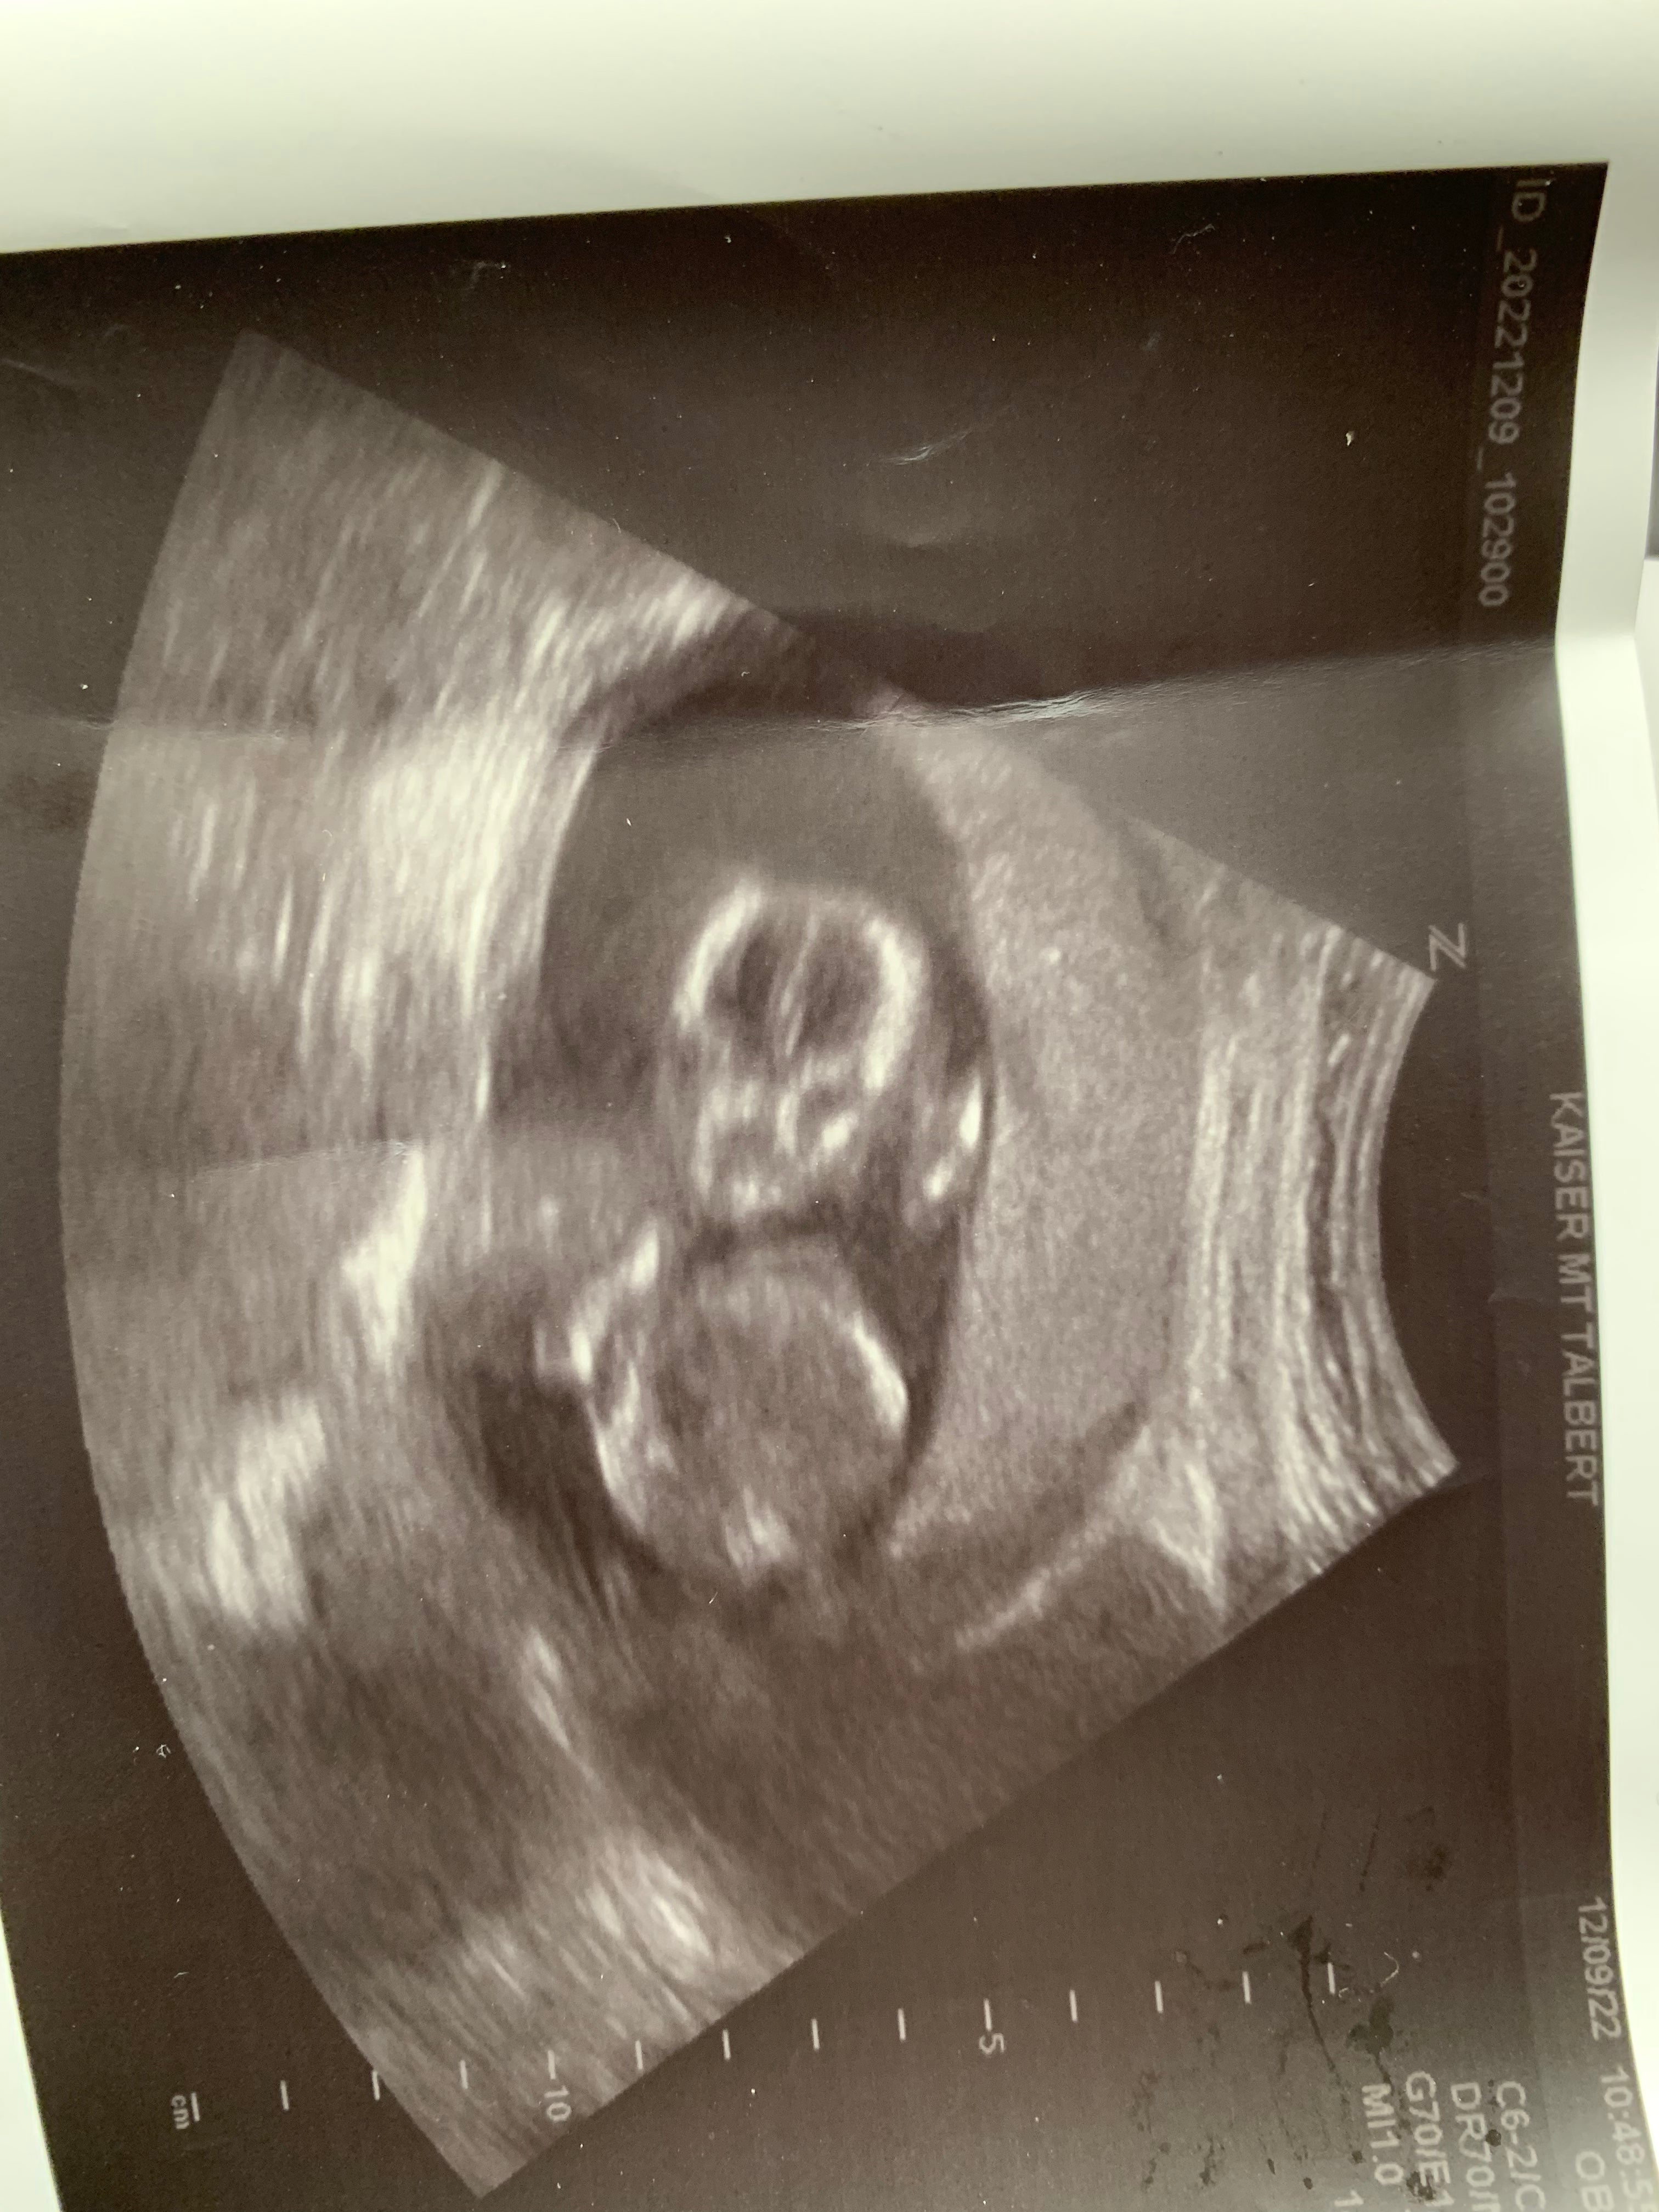

My husband struggles with performance anxiety and the side effects of his prescription medications made TTC difficult and frustrating. Our pregnancy loss in 2021 made this journey even more difficult. I stumbled upon the Mosie website and thought, “what do we have to lose?” Mosie helped take a lot of the pressure out of sex and we were able to enjoy each other and intimacy again. We were pregnant after 5 cycles of using Mosie. We are currently 20 weeks pregnant with our first baby expecting in May 2023!